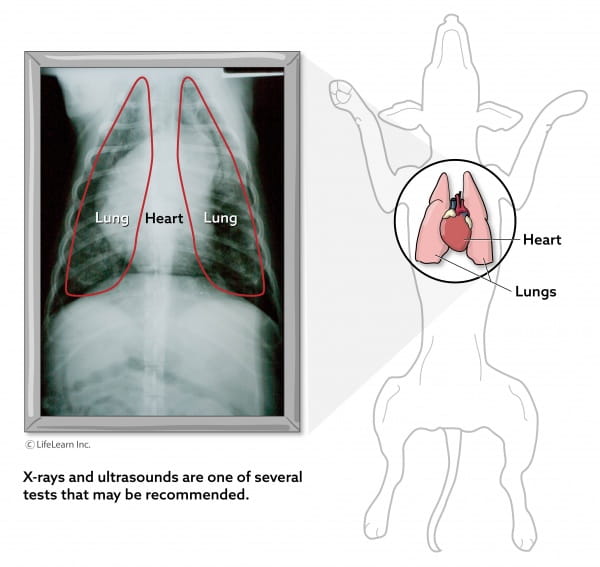

There is no cure for COPD even at. DIAGNOSIS AND THERAPY OF CANINE CHRONIC BRONCHITIS. Diagnostic testing includes physical examina. Typically this leads to a chronic cough that lasts two months or longer – a cough that is not. For somebody with bronchiectasis life expectancy can be a significant concern.

Bronchitis Chronic COPD in Dogs. What Is The Prognosis Life Expectancy Of. Chronic bronchitis is a syndrome defined by cough on most days for at least 2 months for which no specific cause can be identified. Inflammation within airways causes chronic cough and excessive mucus production. Diagnostic testing includes physical examina.